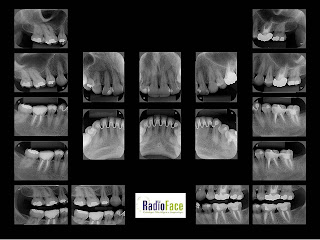

ATM                                                                     Periapical Digital